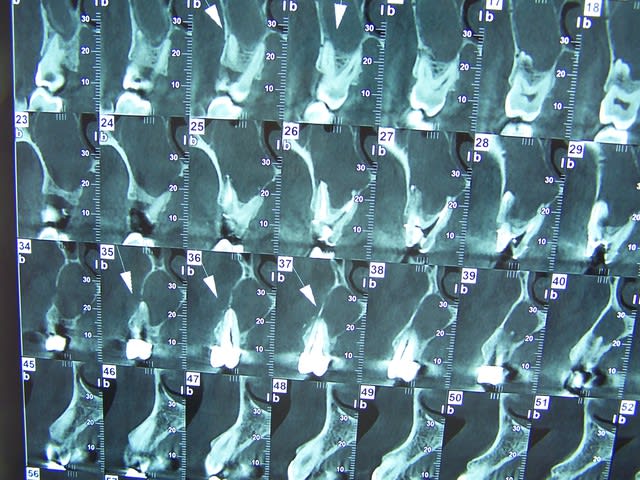

la qualité de tes rétro-alvéolaires est assez étrange... elles sortent comme ca sur ton écran ? C'est tout flou, y'a aucune netteté, on distingue aucun détail.

oui c'est comme ca sur l'écran. c'est un coup d'oeil à prendre mais on s'y fait.

Regarde surtout si tu ne peux pas changer le format d'enregistrement de tes radios. J'ai déjà vu ce type rendu, mais je ne sais plus sous quel format.